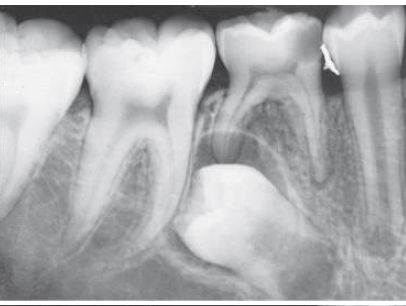

23. Select ONE correct answer.

What is the entity indicated by the arrow?